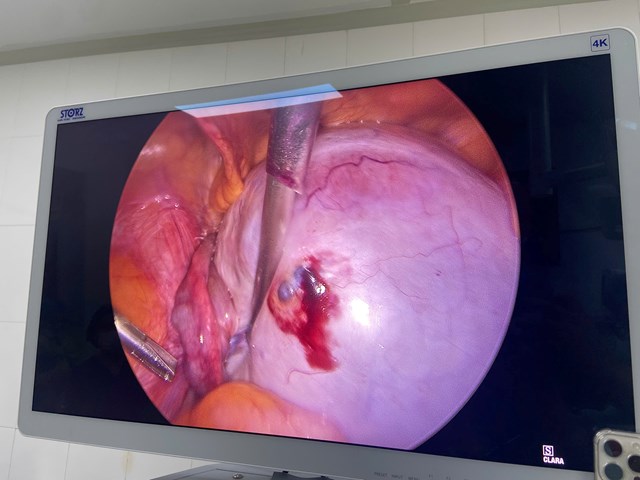

👉 Ê kíp đã tiến hành:

• Tháo xoắn kịp thời → buồng trứng hồng trở lại

• Bóc tách khối u, bảo tồn tối đa phần nhu mô buồng trứng lành